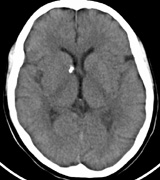

Intracranial leptomeningeal capillary vascular malformation (Figs. 21 and 22) is associated with seizures and contralateral neuromuscular weakness. Central nervous system involvement correlates highly with ipsilateral involvement of the V1 dermatome by a PWS.208,218

Fig. 21. Sturge-Weber syndrome: leptomeningeal vascular malformation.

Fig. 22. Axial T2-weighted (a) and coronal T1-weighted (b) images of a 16-year-old boy with a port-wine lesion over the right side of his face. The right hemisphere is markedly atrophic and abnormal draining veins are seen within the right lateral ventricle (arrowheads). (c, d) The entire right hemisphere is covered by an enhancing pial angioma and the choroid plexi are enlarged. Enhancing retinal angiomas (arrows), typical of Sturge-Weber syndrome, are seen in (d).

It has been hypothesized that the calcific changes reflect cellular anoxic injury secondary to venous stasis/poor drainage.219,220 Abnormal autonomic innervation has also been reported in association with the malformed cortical vessels—innervation only by noradrenergic fibers.221 Studies suggest that the normal increase in brain-blood flow to accommodate increased metabolic demand during seizure activity is blunted in affected brain regions of SWS.222 Thus, seizures in the setting of impaired perfusion may be exacerbating brain injury. Periods of contralateral weakness (days to weeks) can follow a prolonged seizure episode.206,223